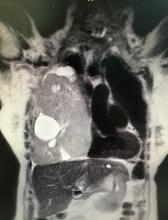

[3]Figure 1. Coronal section of computed tomography, where heterogeneous lesion with cystic area is observed, which displaces the mediastinum, collapses the lung, and flattens the diaphragm.

The physical examination showed the abolition of vesicular murmur in the lower, middle, and part of the upper pulmonary field. She brought spirometry with severe restrictive pattern. Thoracic computed tomography (CT) was performed, where a heterogeneous voluminous mass was observed, with cystic areas, in the right lung, 126 x 166 mm in size, in intimate contact with the thoracic wall, diaphragm, and mediastinal structures (figure 1).